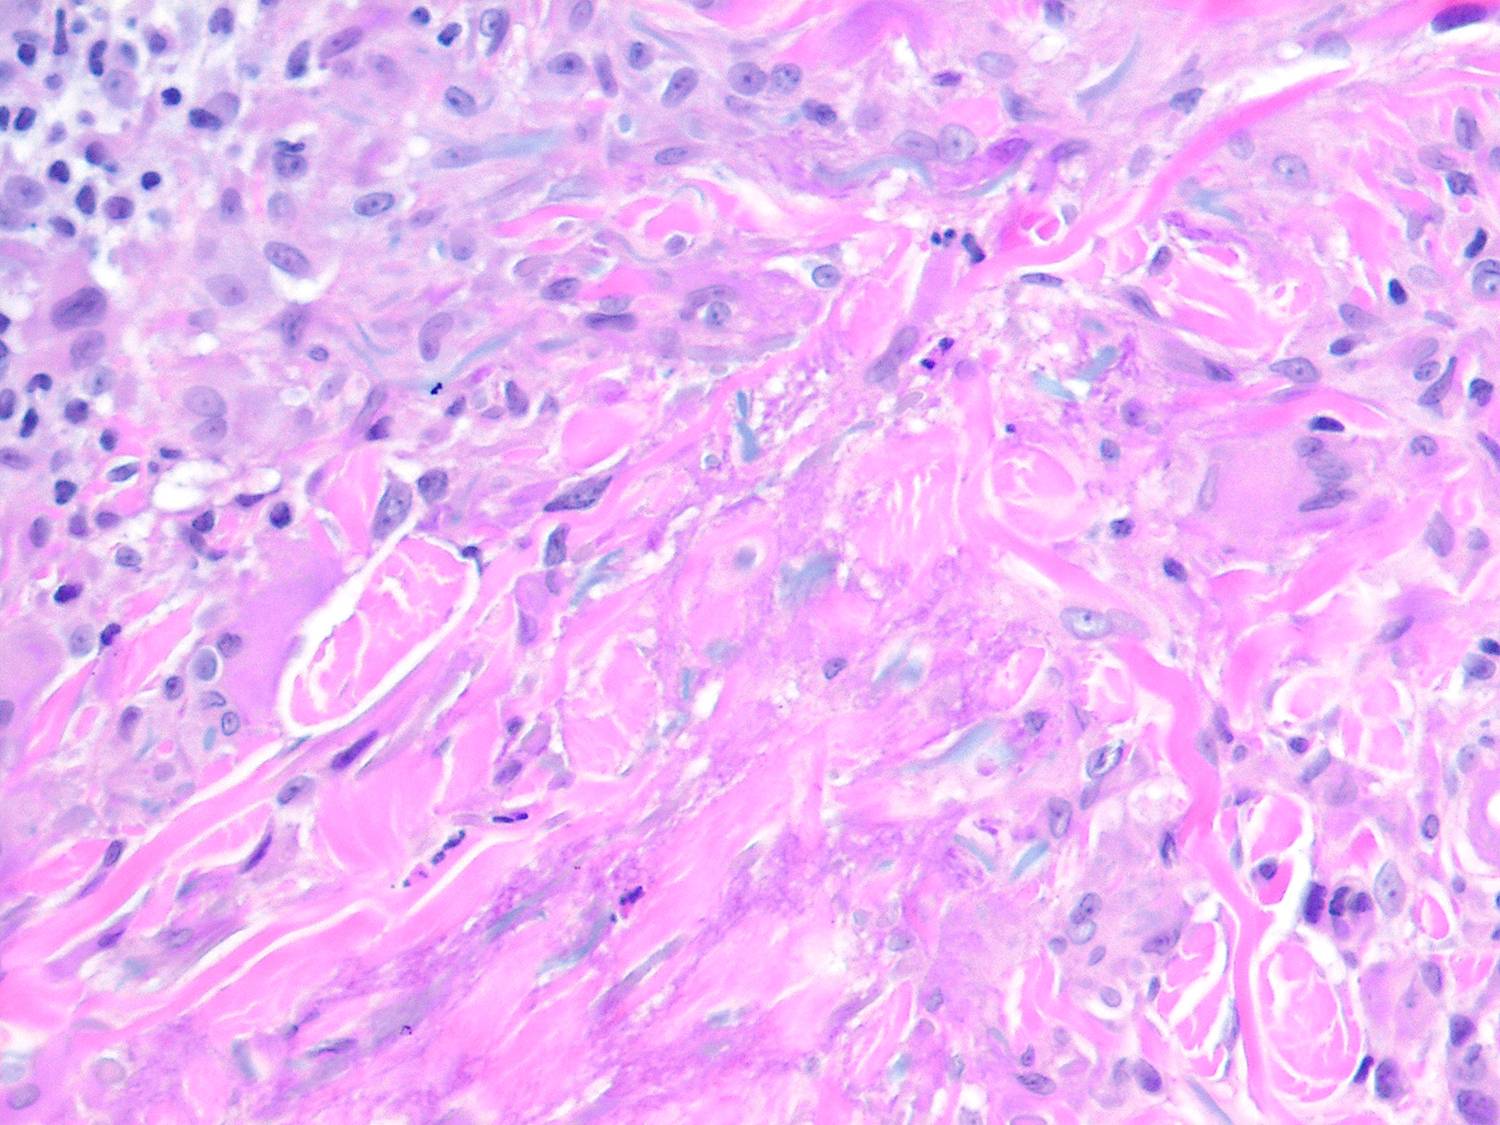

Annular elastic granuloma =الورم الحبيبي الحلقي المرن